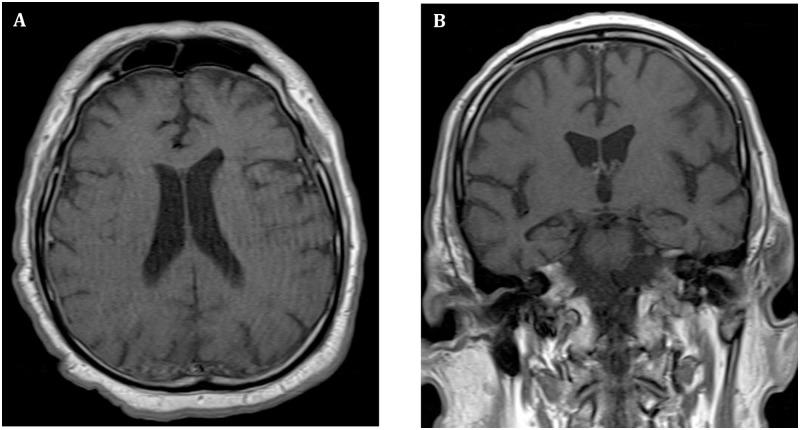

Central and peripheral nervous system involvement caused by Zika and chikungunya coinfection.

PLoS Negl Trop Dis. 2017 Jul 13;11(7):e0005583. doi: 10.1371/journal.pntd.0005583. eCollection 2017 Jul.